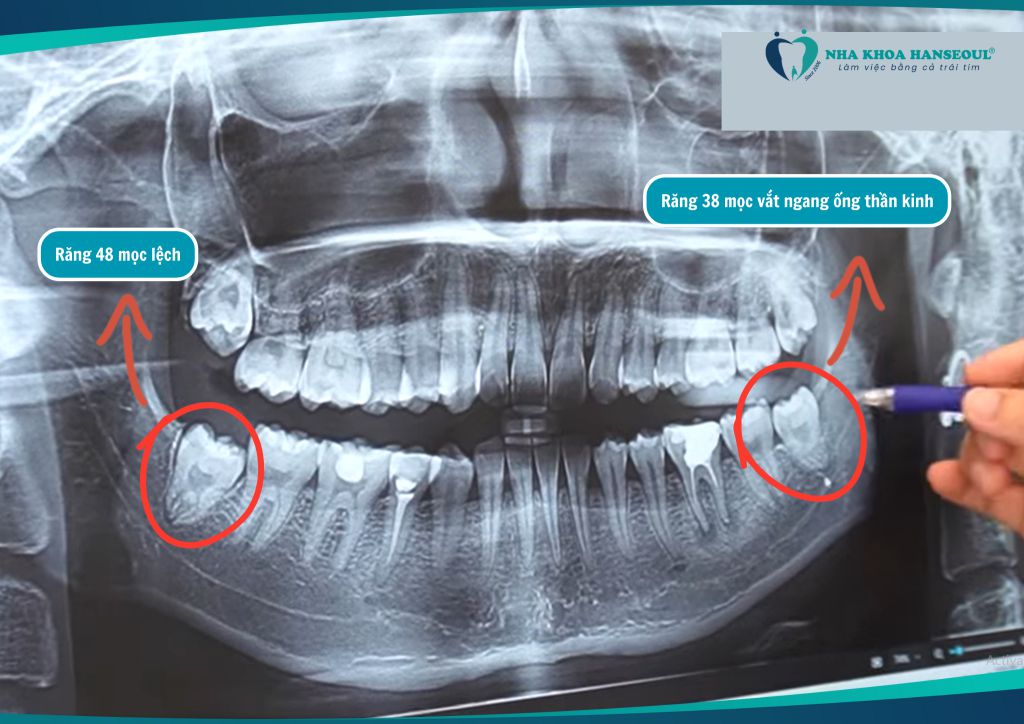

Bạn Dung (21 tuổi) đến với Nha khoa Hanseoul trong tình trạng sưng đau hàm bên trái. Sau khi chụp phim và thăm khám kỹ lưỡng, bác sĩ chẩn đoán cả 4 chiếc răng số 8 của bạn đều cần phải nhổ bỏ, trong đó:

- Răng 38 mọc vắt ngang ống thần kinh – rất nguy hiểm nếu không xử lý đúng kỹ thuật.

- Răng 48 mọc lệch gây chèn ép, viêm đau và khó vệ sinh.